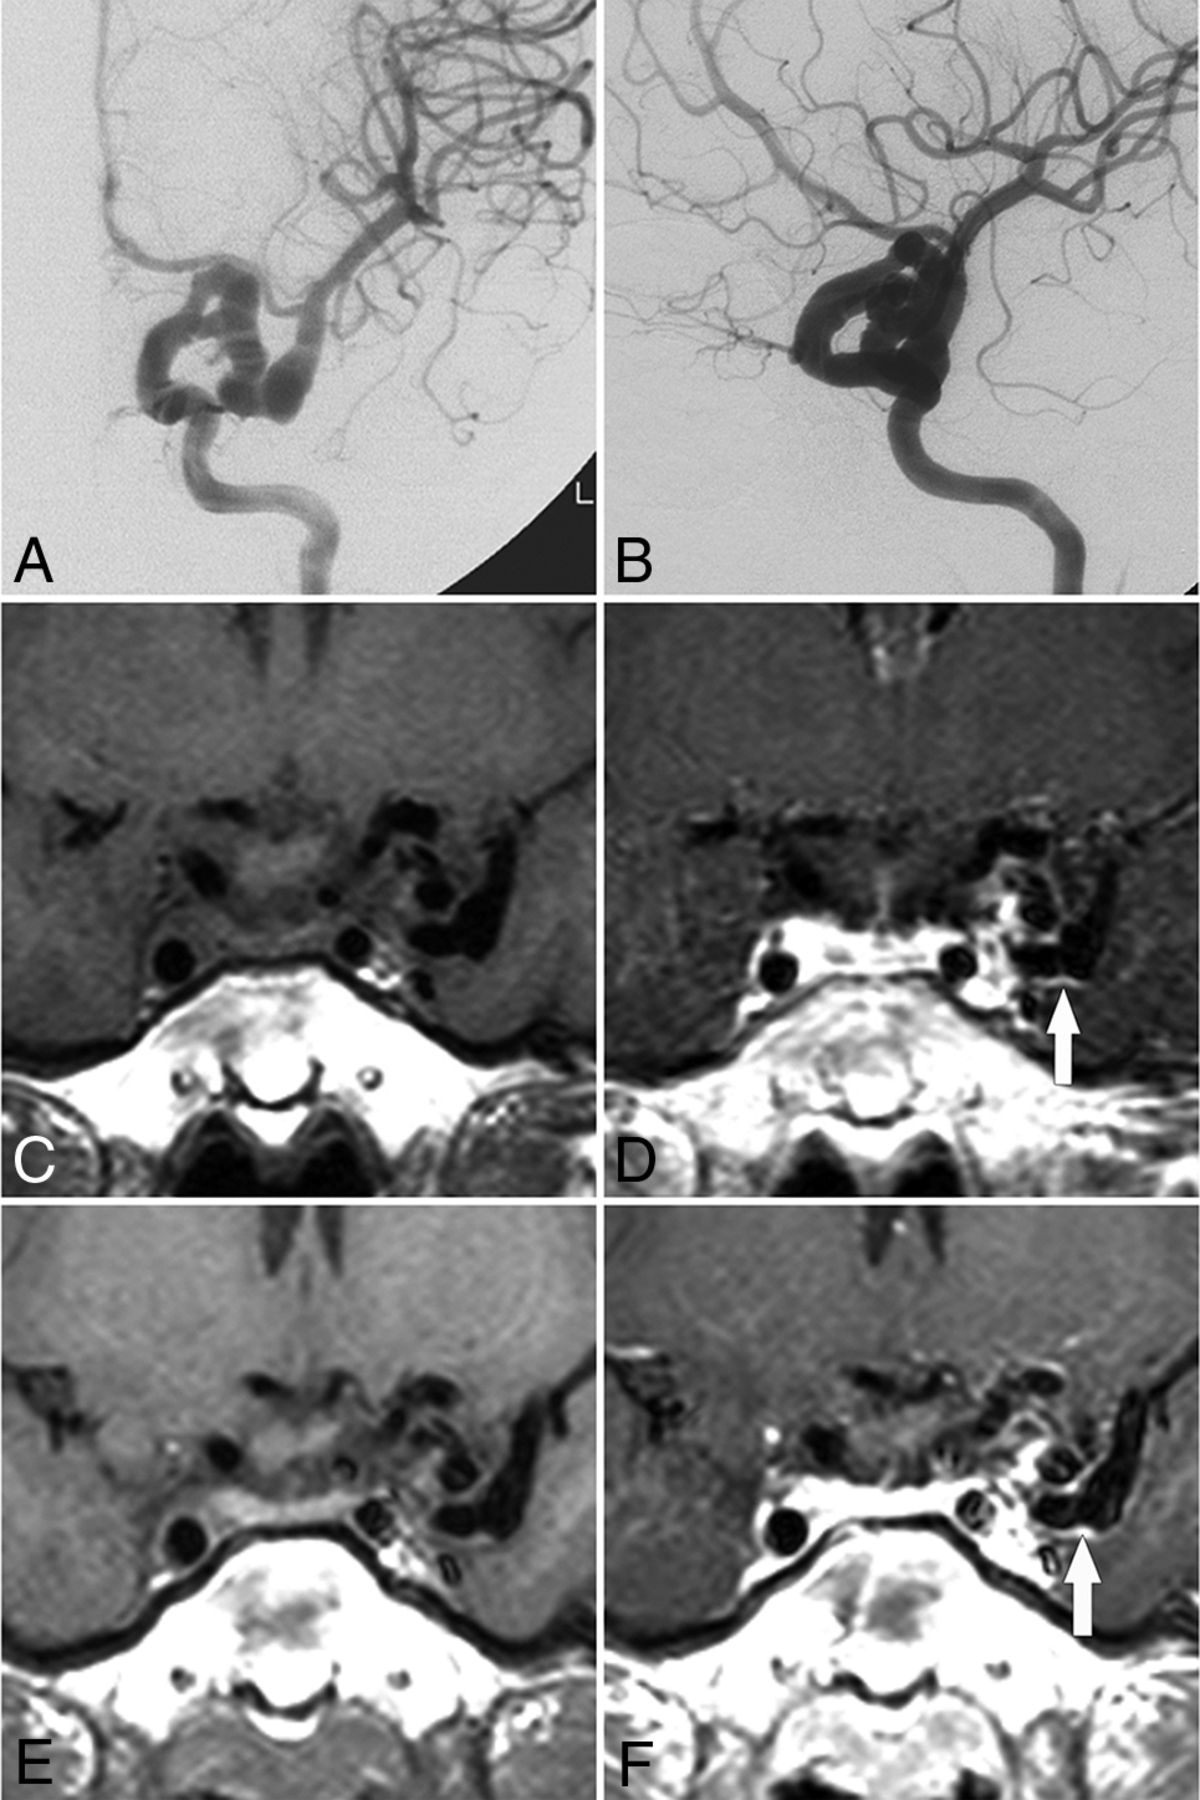

Vessel wall enhancement at the aneurysm wall and the parent artery wall in a patient without PHACE syndrome (patient 11, a 45-year-old woman). A–C, Cerebral angiography shows dolichoectasia in the right distal ICA and basilar artery. D, 3D-DSA shows dolichoectasia in the right distal ICA and right PcomA as well as the formation of multiple aneurysms in the right PcomA (arrow). E and F, Non-contrast-enhanced and contrast-enhanced vessel wall imaging shows enhancement of the aneurysm wall (arrows in F) and the parent artery wall (curved arrow in F).

We believe that attention should be paid to several cases in this study. One patient (patient 1) exhibited simultaneous vessel wall enhancement and calcification at 7 years of age, leading to our hypothesis that the affected vessel wall was prone to atherosclerosis formation and secondary calcification. Questions also remain regarding the use of antiatherosclerosis therapies in young patients. Another patient (patient 11, Fig 5) exhibited vessel wall enhancement in an aneurysm and its parent artery, which may be a risk factor for aneurysm rupture; accordingly, a pre-emptive aneurysm embolization was performed.24 In another patient (patient 16), asymptomatic ICDE of the right ICA and hypoplasia of the right A1 segment were detected at 54 years of age, and a blood flow–related aneurysm of the left anterior communicating artery was observed at 69 years of age. This patient was later treated with coiling embolization. Therefore, we suggested a follow-up comprising regular angiography studies (CTA or MRA) to demonstrate overall luminal changes and, if possible, vessel wall imaging to detect inflammation in the lesion.